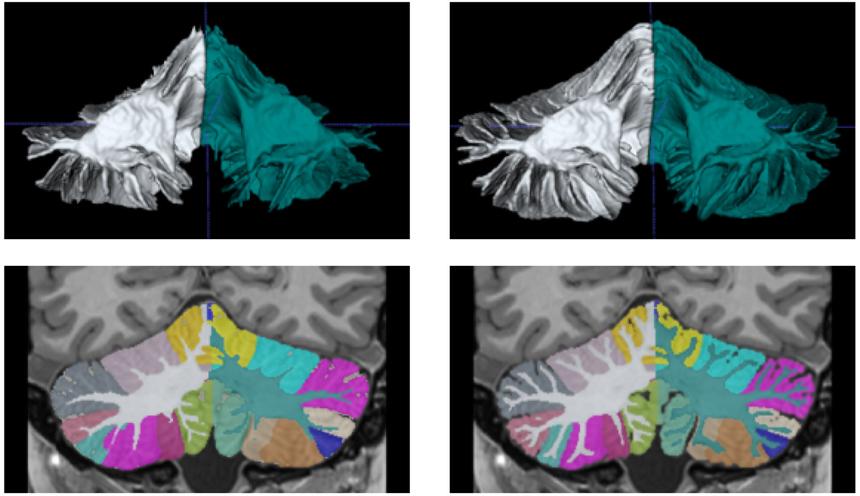

Программа DeepCeres использует ИИ для создания изображений в высоком разрешении и помогает исследовать такие заболевания, как болезнь Альцгеймера, шизофрения, аутизм и боковой амиотрофический склероз (БАС). Исследование было опубликовано в журнале NeuroImage.

DeepCeres решает эту проблему, используя нейросети для преобразования стандартных снимков в сверхвысокое разрешение. Это позволяет исследователям и врачам получать детализированные изображения мозжечка без необходимости в дорогостоящем оборудовании.

Разработчики отмечают, что DeepCeres способен точно измерять 27 различных структур мозжечка. Это открывает новые возможности для диагностики и изучения неврологических и психиатрических заболеваний, а также помогает исследовать роль мозжечка в развитии нейродегенеративных патологий.